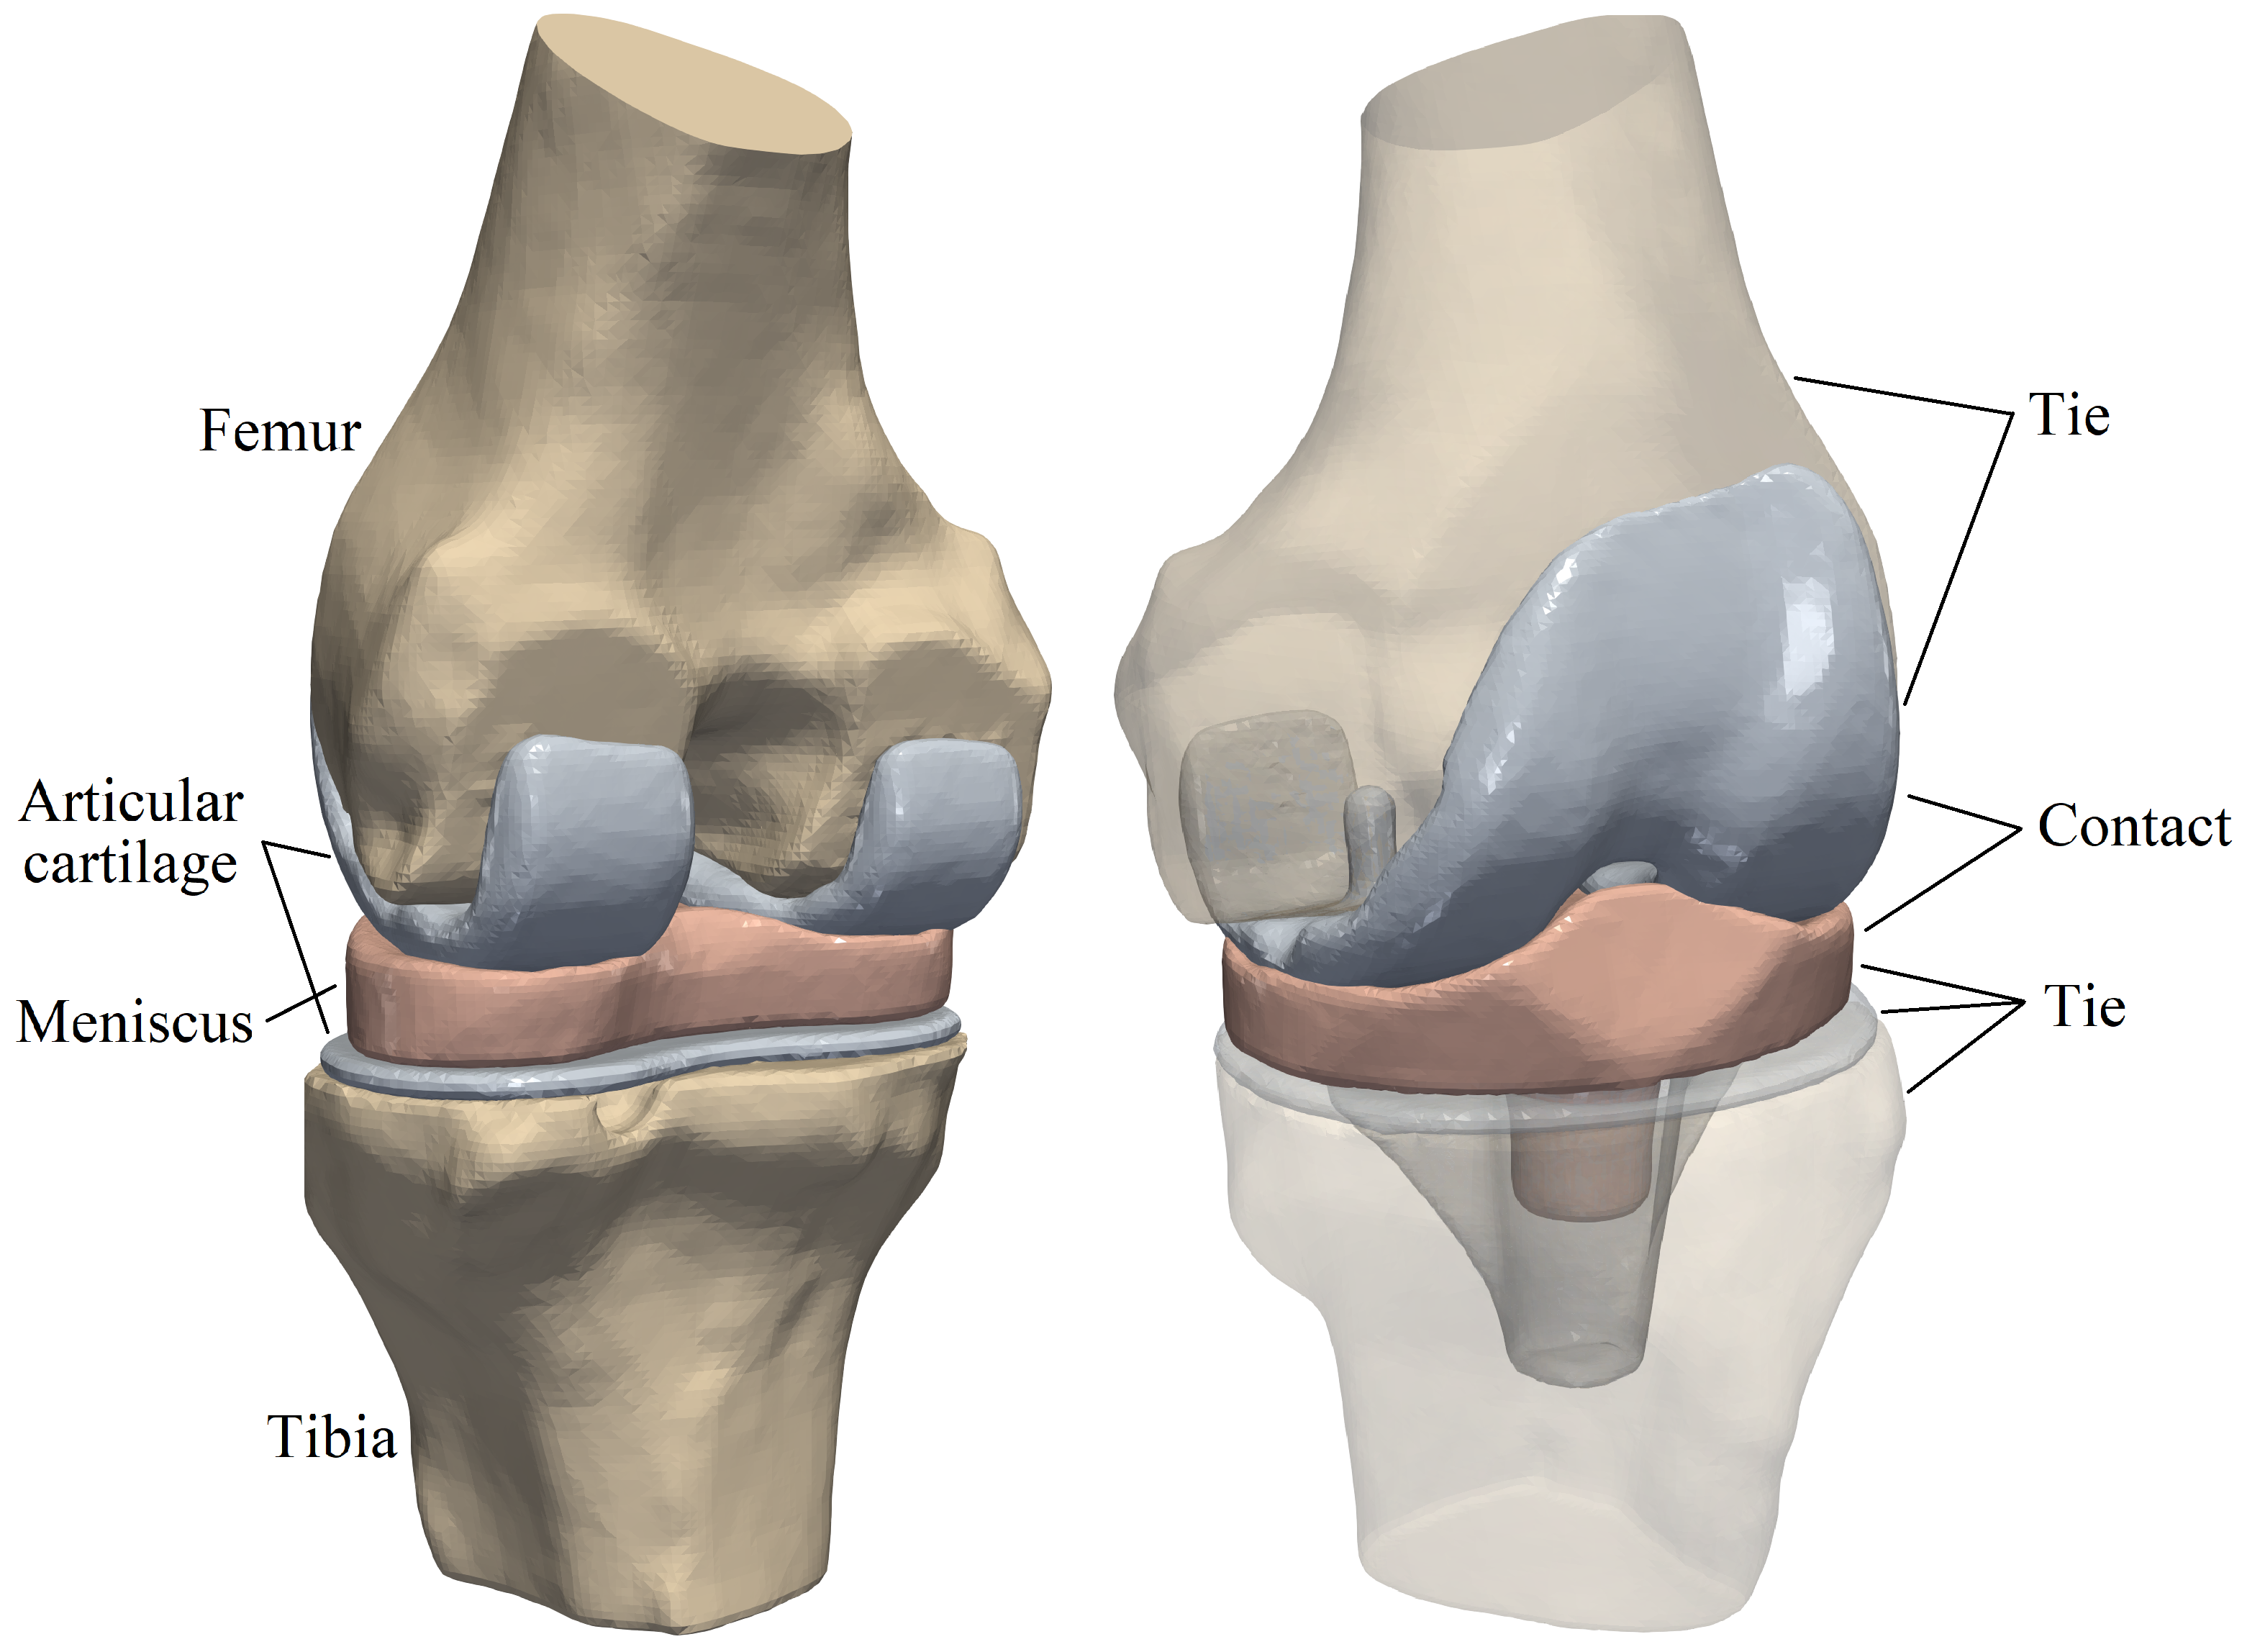

A knee joint given in STL format [70] is considered for performing a contact analysis. The knee joint is composed of femur and tibia, a meniscus and two articular cartilages as illustrated in Fig. 30. The femur and the tibia are covered with articular cartilages, thus the interactions between bones and articular cartilages can be treated as perfect bond (tie constraint in ABAQUS). The meniscus is inserted into the articular cartilage covering the tibia, thus the interaction between them can also be regarded as perfect bond. The interaction between the meniscus and the articular cartilage covering the femur is treated as contact.

The mesh generated by the octree algorithm with trimming [29] is shown in Fig. 31. The base sizes are and for the contact parts and other parts, respectively. There are 253,079 elements and 361,296 nodes, and the number of nodes in one element varies from 4 to 27. A slice in the vertical plane passing the geometrical center is also shown in Fig. 31. The contact interface meshes are non-matching for this example, because the contact domains are geometrically non-conforming and large sliding might occurs at the interface during the loading process. The meshes generated through the STL-based octree algorithm are suitable for contact analysis. In the standard FEM, local mesh refinement may be required to generate finer meshes on the contact surfaces. However, in an automatic manner, octree cells with fast mesh size transition can be generated through the octree mesh generation technique. Compared to the interior elements, the elements near the boundaries are smaller, which will generate more accurate surfaces for tie constraints and contact pairs. Besides, compared to the image-based technique, the STL-based octree algorithm allows trimming on the octree cells, which leads to more accurate meshes representing complex boundaries especially for curved shapes.

The tissue material properties in the computational modeling of human knee joints have been studied in Ref. [71], however, there are considerable variations of the material properties within the wide body of literature. The mechanical properties used in this example are mainly taken from Ref. [72] and are listed in Table 9. The contact is STS contact with a friction coefficient of [73].

| Femur | Tibia | Articular cartilage | Meniscus | |

|---|---|---|---|---|

| Young’s modulus | ||||

| Poisson’s ratio | 0.2 | 0.2 | 0.25 | 0.35 |

The bottom surface of the tibia head is fixed, and two translational DOFs in the horizontal plane of the top surface of the femur head are also constrained. On the top surface of the femur head, a vertical load of up to [72] is applied to induce contact in the knee joint. The displacement contours () from different views are shown in Fig. 32. It is obvious that the deformation occurs mainly in the meniscus. The femur, tibia and articular cartilages are similar to rigid bodies. This phenomenon meets the expectation because the Young’s modulus of the meniscus is significantly smaller than those of the bones and articular cartilages. The meniscus is squeezed into the joint space and there is lateral extension of the meniscus. The large deformation of the meniscus increases the contact area which is helpful to reduce the contact pressure.

The contact pressure distributions () are depicted in Fig. 33. To illustrate the distribution clearly, contact pressure values smaller than are not included in the contour. It is obvious that the contact pressure on the articular cartilage has a similar distribution and magnitude compared to that on the meniscus. Besides, the contact pressure on the articular cartilage has a similar distribution from Ref. [72].

The development of the contact on the articular cartilage is recorded, as depicted in Fig. 34. Note that only the area where the contact pressure is greater than has been taken into account. Generally speaking, with increasing the vertical load , the contact area is increasing while its increasing rate is reducing. The average contact pressure increases during the loading history. Before the vertical load increases up to , the increasing rate of the average contact pressure is basically reducing. However, when the average contact pressure increases almost linearly because the contact area increases only slightly.

The total CPU time of this example is 16.68 hours, in which 0.90 hours are spent on the element analysis of UEL. The UEL time comprises of 0.52 hours on the pre-calculation and 0.38 hours on the step of nonlinear analysis. It accounts for only 5.4% of the total CPU time.